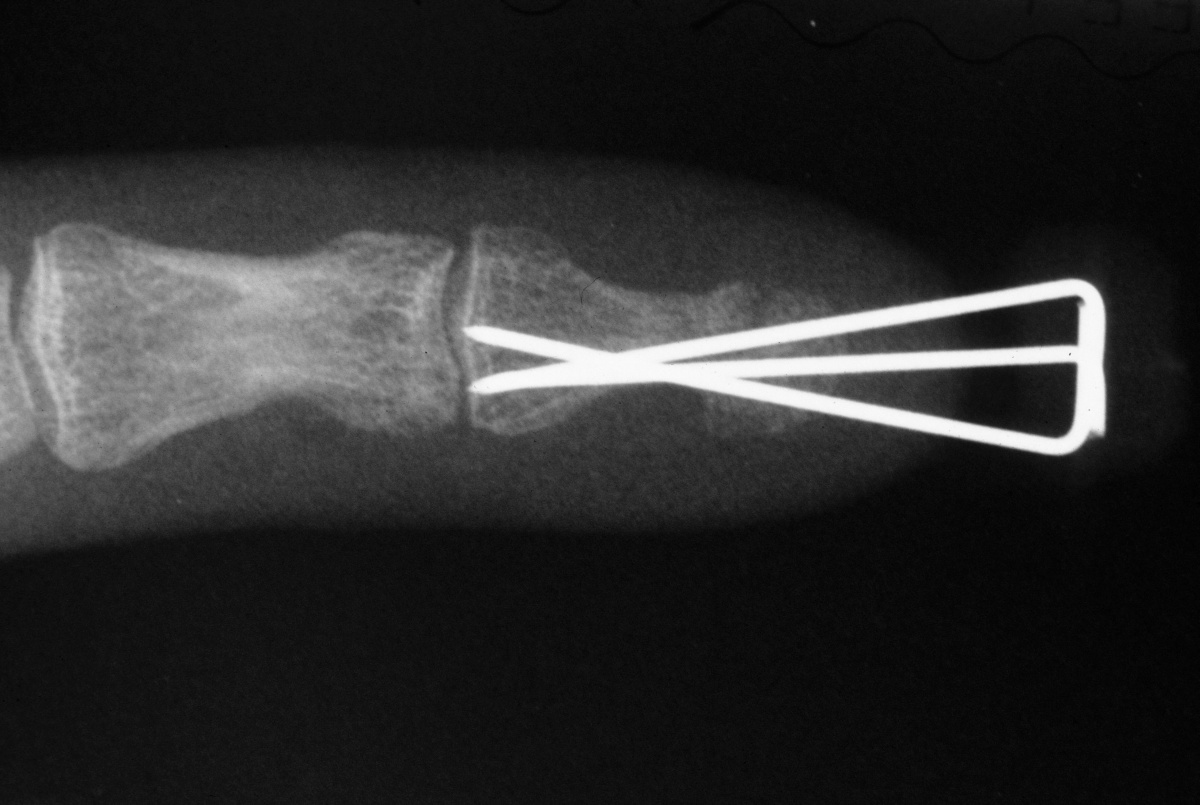

| Case 2. 3 month old grossly unstable nonunion. |

| The new nail plate

is visible growing deep to the original nail plate. |

| The distal nail

plate fragment was removed, and the fracture was

stabilized with K-wires as in case 1. |